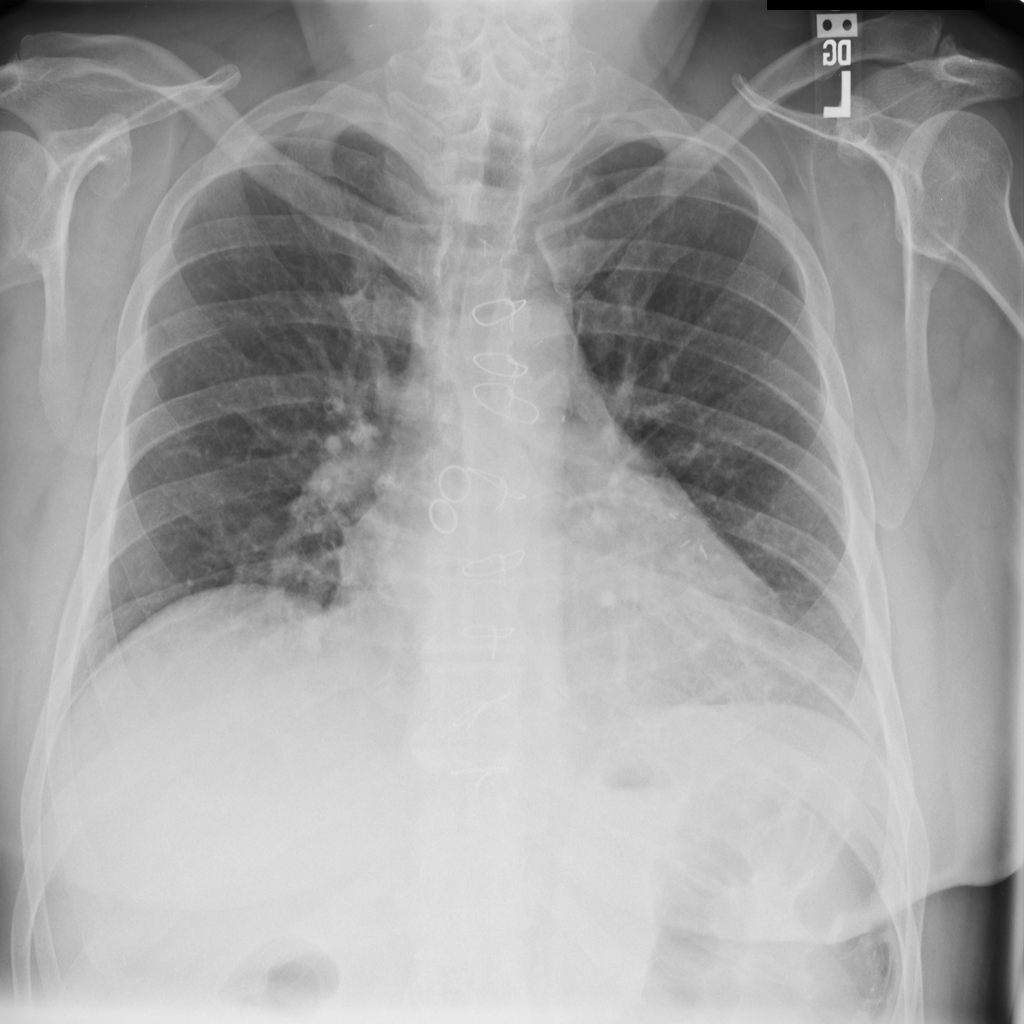

PAT-AE5C · IMG-000Cardiomegaly

PAT-AE5C · IMG-000

PA